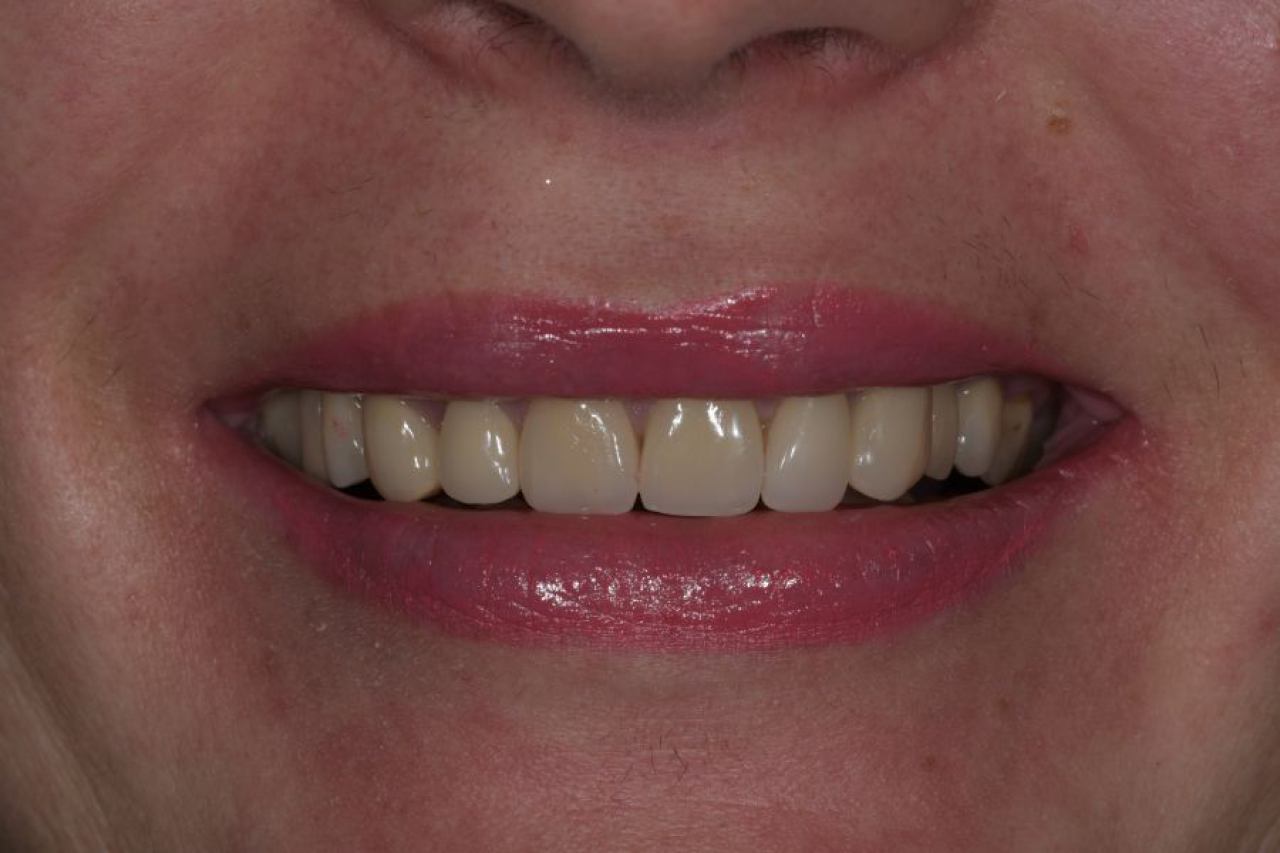

Estetska dentalna medicina

Izbjeljivanje zubi i zubne ljuskice zaštitni su znak Hollywoodskog osmijeha. Izbjeljivanje nije štetno za zube i ne oštećuje caklinu.

Ukoliko niste zadovoljni svojim osmijehom tu je DSD ili Digital Smile Design kojim u okvirima naših mogućnosti ispunjavamo vaše želje „Hollywood smile" ljuskicama, minimalno invanzivnim preparacijama zuba.

Marković Dental Clinic uvijek na prvom mjestu ima zdravlje zubi i zadovoljstvo svakog pacijenta. Koristimo najmoderniji software gdje je pacijentu moguće virtualno prikazati nove zube te kasnije kreirati novi osmijeh protetskim radom, ljuskicama, krunicama ili mostovima.